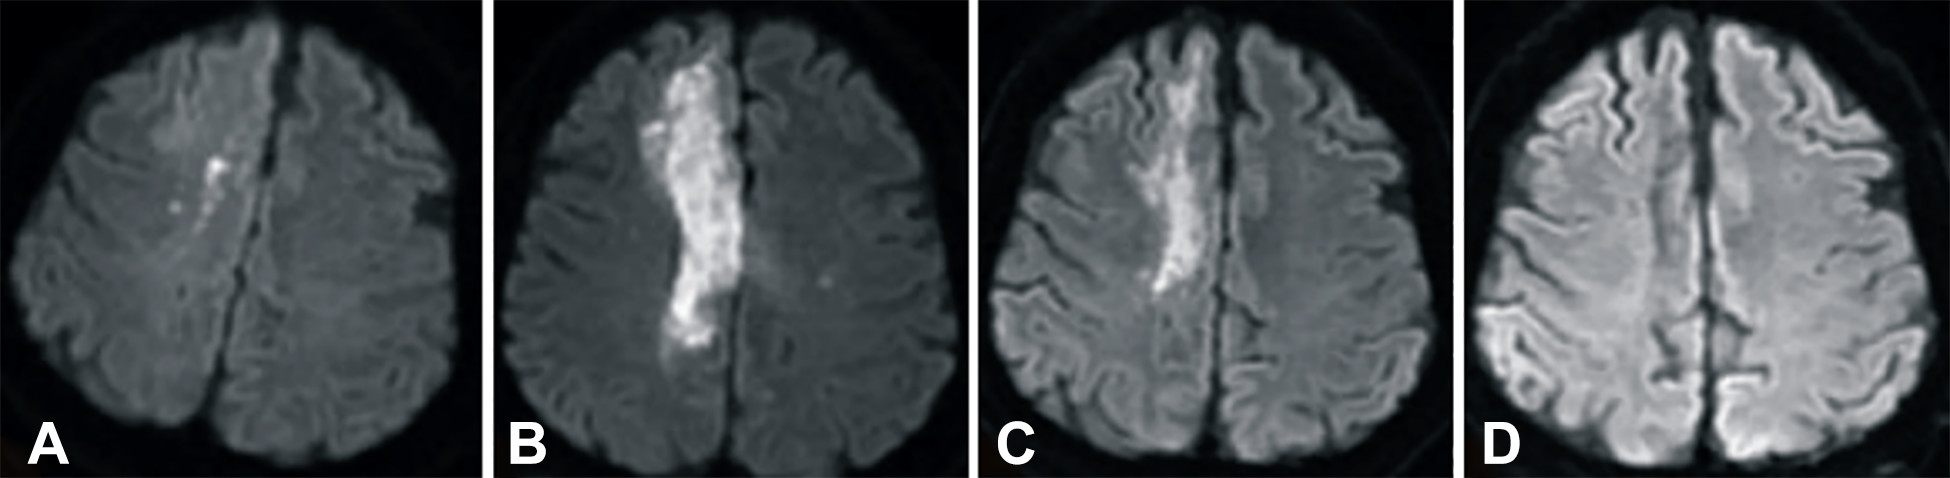

發(fā)病后2小時和8天行彌散加權(quán)成像(DWI)檢查,發(fā)現(xiàn)右側(cè)放射冠梗塞(白色信號增加),3個月后梗塞散在,6個月后消失(圖2A-D)。

卒中發(fā)病后2小時和單核細(xì)胞臍帶血輸注后6個月獲得的彌散加權(quán)圖像

圖2 . 卒中發(fā)病后2小時和單核細(xì)胞臍帶血輸注后6個月獲得的彌散加權(quán)圖像。(A)卒中后2小時,(B)臍帶血輸注后1天,(C)臍帶血輸注后3 個月,(D)單核細(xì)胞輸注后6個月